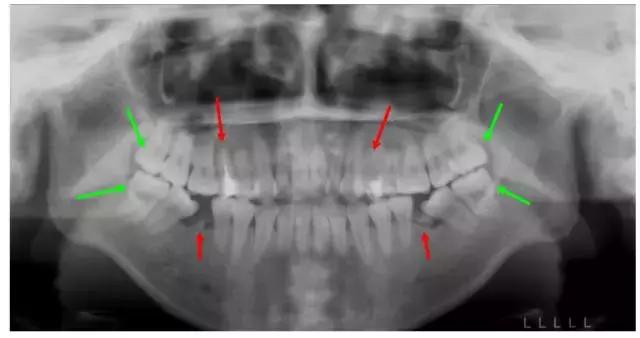

这个妹子正畸前,前牙不能咬合,牙凸又嘴凸而且还有残余的牙根,牙列开始倾斜。综合考虑后,医生拔除了箭头所示8颗牙,没有采取常规拔牙,因为需要尽量拔除不能保留的病牙。

矫正结束后,姑娘收获了整齐的牙齿和完美的微笑~